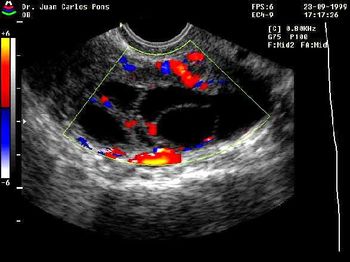

This is a confirmed case of scar ectopic pregnancy. Yesterday, I carried out this exam in an emergency room, without much time to perform an adequate sonogram, the patient did not feel good with “cramps” but no signs of bleeding.